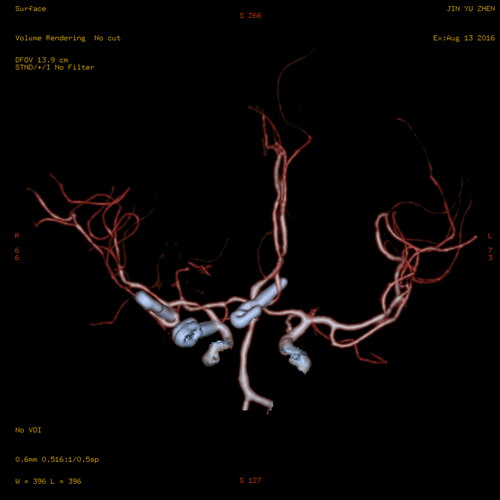

图为患者术后CTA检查提示右后交通动脉瘤瘤夹、右大脑中动脉瘤瘤夹、前(偏左)交通动脉瘤瘤夹

该患者因突发剧烈的持续性头痛,且感到左手指末端麻木不适,前往当地医院就诊,被诊断出蛛网膜下腔出血。随后转院至临床医学院/附属医院进行治疗,行全脑血管造影术显示右后交通动脉瘤、右大脑中动脉瘤、前(偏左)交通动脉瘤及右大脑中动脉中到重度狭窄。考虑到颅内三处动脉瘤随时可能发生破裂而危及生命,手术及其复杂而且风险性非常高,神经外科赵浪平主任立即组织全科医生讨论,制定最佳手术治疗方案并征得家属同意。